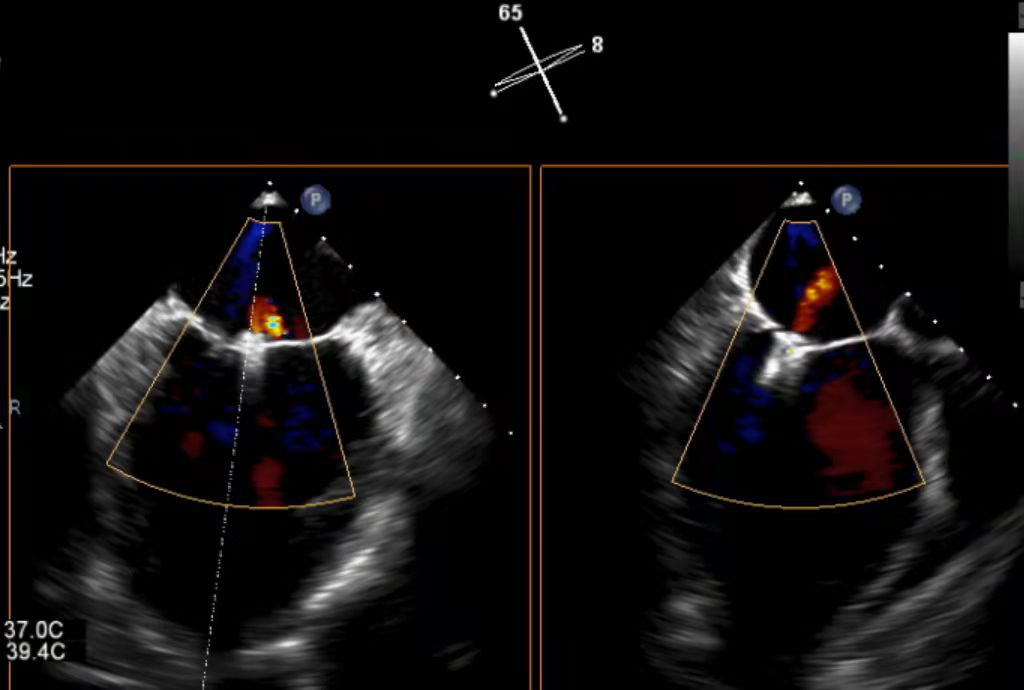

患者为47岁男性患者,受活动后胸闷气短困扰七年余,诊断为扩张型心肌病、心脏扩大、二尖瓣反流(重度),优化药物治疗后仍反复活动后气促,术前经胸超声心电图检查提示二尖瓣中重度反流,左室舒张末径66mm,左室收缩末径56mm,左室射血分数35%,缩流颈宽度0.65cm, 有效反流口面积0.49cm²,二尖瓣瓣口面积4.81cm²,心功能不全表现严重。

术前心超